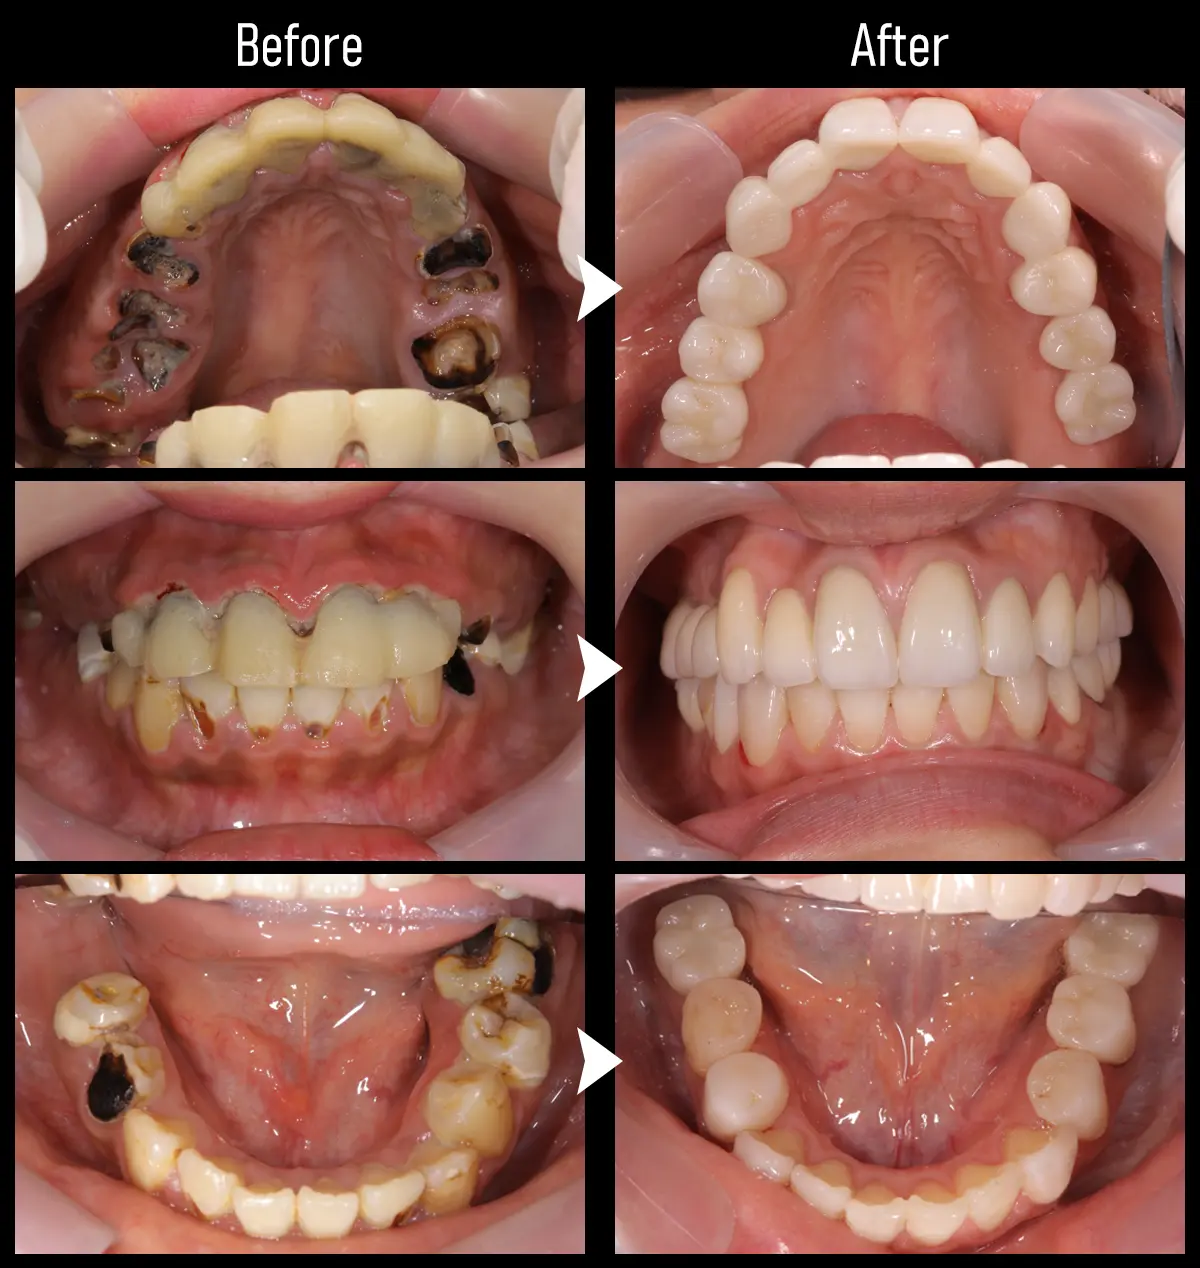

CASE:フルマウス

症例All-on-4(オール・オン・フォー)

主訴 奥歯がない

治療内容 上下合計11本のインプラント治療を行い、全顎治療を実施

標準費用(自費) 781万円